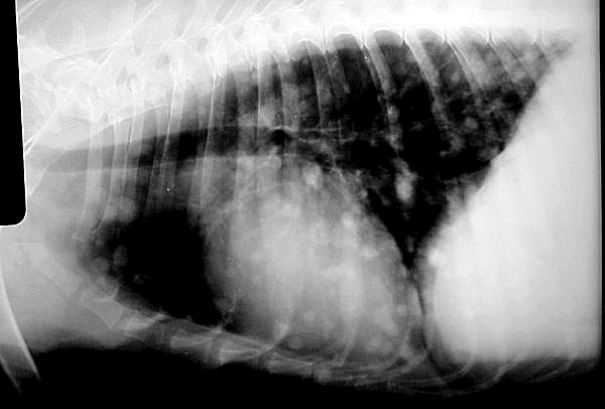

Tüdő daganat

Áttétes tüdődaganat

Előfordulhat primer tüdődaganat, amikor a daganatos sejtek képződése a tüdő szövetében kezdődik. Ilyen esetekben – ha a daganat kellően körülhatárolt és nem érint túl nagy tüdőterületet – szóba jöhet a daganatos tüdőterület műtéti eltávolítása. Azokban az esetekben amikor a test más részén kialakult daganat képez áttétet a tüdőbe (metasztázis), sajnos a műtéti eltávolítás már nem jelent kezelési lehetőséget.